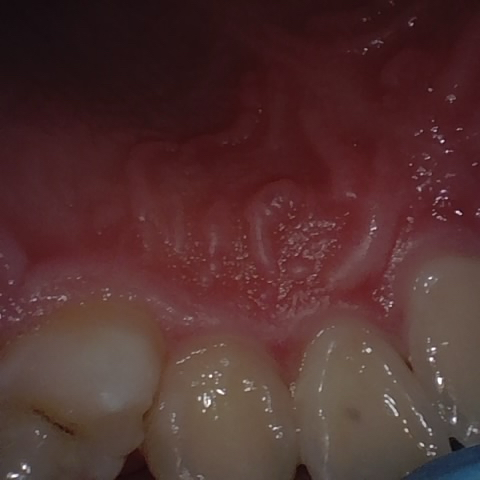

Annotated as "Good"